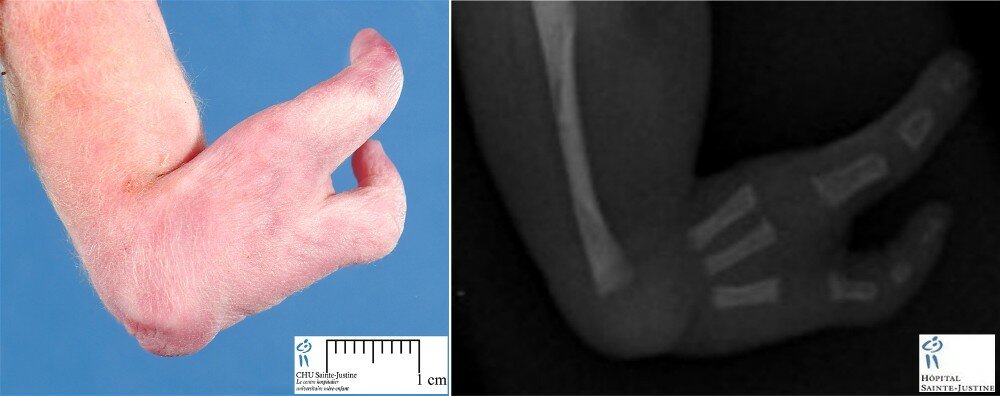

Case 10516: Sirenomelia with upper limb anomalies